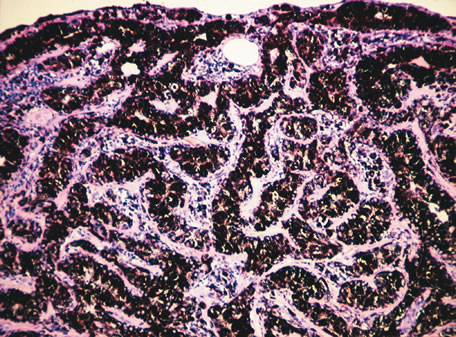

Inflammatory conditions may also lead to iris nodules. Patients suffering from fungal endophthalmitis may demonstrate an irregular yellow-white mass on the iris. Histologically, these appear as necrotizing granulomas containing mycotic agents (Fig. 2). In juvenile xanthogranuloma, a yellowish-gray iris lesion may be associated with spontaneous hyphema, and histopathologically the nodules demonstrate diffuse histiocytic infiltrate (Fig. 3). Multinucleated giant cells displaying peripheral foamy cytoplasm are also noted; these cells are known as Touton giant cells.29 The giant cells and the histiocytes contain lipid that can be demonstrated by oil red O stain.

Fig. 2. Coccidioidomycosis. Iris stroma shows necrotizing granuloma containing mycotic organisms. The organisms show features of Coccidioides immitis. (Hemotoxylin-eosin ×60.)